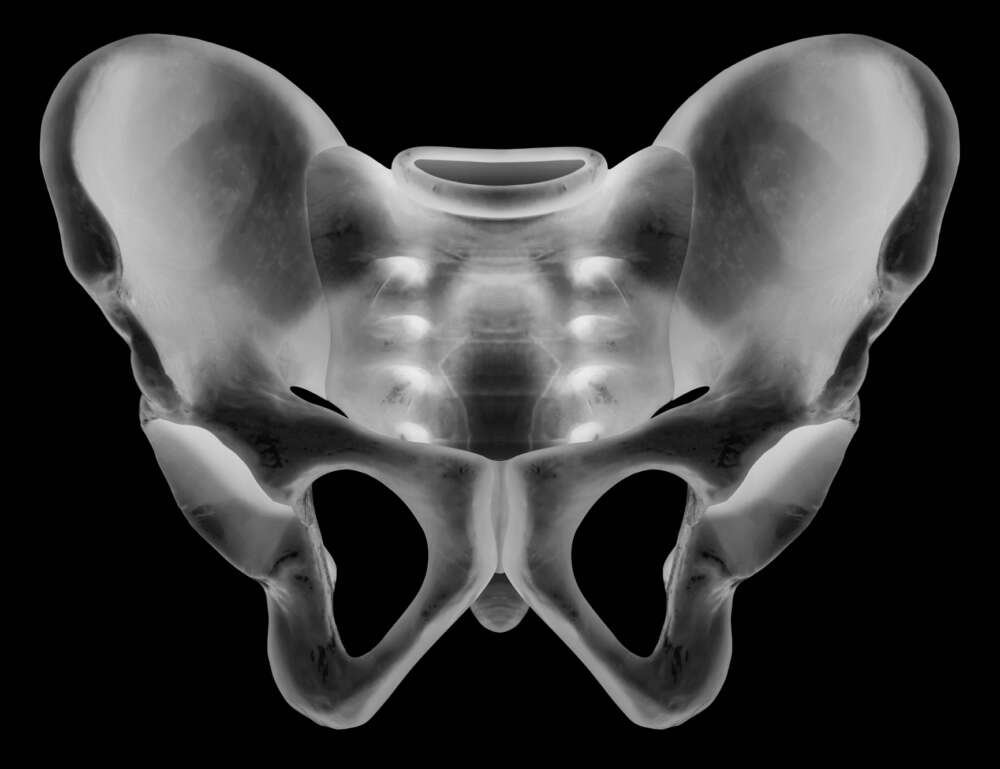

In der Regel ist die erste Behandlung konservativ mit Schmerzmitteln und Unterstützung bei der Mobilisation. Leider können diese Verletzungen aber auch zu chronischen Schmerzen und Verlust der Selbstständigkeit und Gehfähigkeit führen. Die Ursache liegt darin, dass meist auch das hintere Kreuzbein mitverletzt ist und der Belastung nicht mehr standhalten kann. Dies kann dazu führen, dass die Brüche nicht mehr heilen. Die Frakturen werden in der Literatur als "Fragility Fractures of the Pelvis (FFP)" oder "Insuffizienzfrakturen" bezeichnet, da sie meist mit einer Osteoporose vergesellschaftet sind.

Die Behandlung der verzögerten Heilung und der Instabilität besteht in einer chirurgischen Stabilisierung des hinteren Beckenrings mit zwei Schrauben, welche das Becken wieder mit der Wirbelsäule stabil verbinden. Die Schrauben können perkutan eingebracht werden, führen zu einer sofortigen Schmerzlinderung und ermöglichen es somit den Knochenbrüchen zu heilen. Die meisten Patienten sind nach dem Eingriff in der Lage, ohne Schmerzen zu gehen. Die Belastung für den Patienten ist dank der Schlüssellochchirurgie minimal und dauert weniger als eine Stunde.